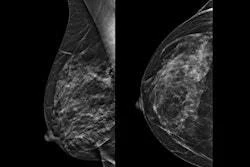

QT Imaging Holdings has released an upgrade to its image reconstruction software, QTscan, for use with its QTI Breast Acoustic CT.

QTscan version 4.4.0 reduces image processing time, according to the firm. It is optimized for systems that use NVIDIA's L40 GPUs, which are driven by the Ada Lovelace architecture.